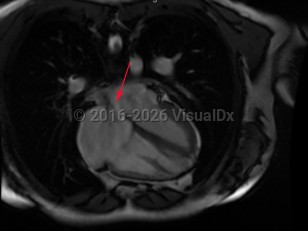

The presence of a defect (opening) in the septum that separates the 2 atria of the heart with resultant flow. It can be congenital or acquired. Associated clinical issues may include flow of oxygenated blood from the left atrium to the right atrium, producing a volume overload on the right heart; flow of unoxygenated blood from the right atrium to the left atrium resulting in cyanosis; and/or traverse of emboli from the venous circulation to systemic circulation, causing a stroke, transient ischemic attack, or other embolic events.

Atrial septal defect